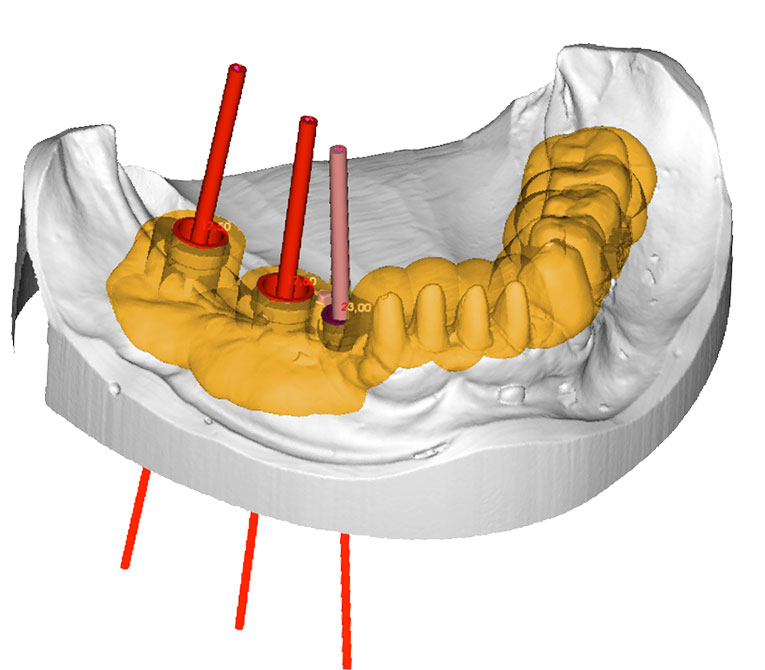

Kurs digitale Abfor- mung für Zahnärzte / Helferinnenneu3D-Planungs-Software

Training Implantatsoftware multiple SystemeneuDVT Fachkunde